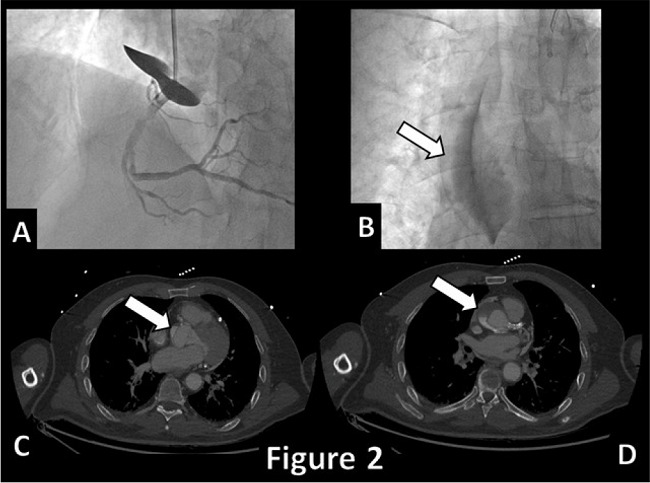

During the last procedure, the patient developed a dissection of the proximal part of the RCA (Video 2) that rapidly extended upward to the ascending aorta (Figure 2). An emergency computed tomography (CT) scan showed the progression of the dissection to the innominate and the left common carotid arteries. At the end, he underwent emergency ascending aorta replacement surgery with a #24 Dacron tube prosthesis. The postoperative course was characterized by a minor stroke on the right parietal territory with no clinical remarks at the discharge, on the 7th postoperative day.